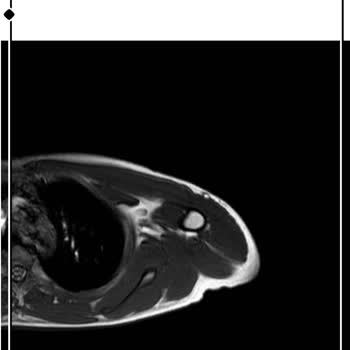

26 Aralık Cuma günü saat 19.00–20.00 aralığında Sefaköy Medipol Hastanesi aciline başvurdum. Acilde tansiyonum 17 olarak ölçüldü, ardından üst kata kadın doğuma çıktım. N**** Ö****** Y***** nöbetçiydi. Zaten iki gün önce muayene ve ölçümlerim yapılmış, oranın takipli hastasıyım. Kadın doğum servisi...

doktor